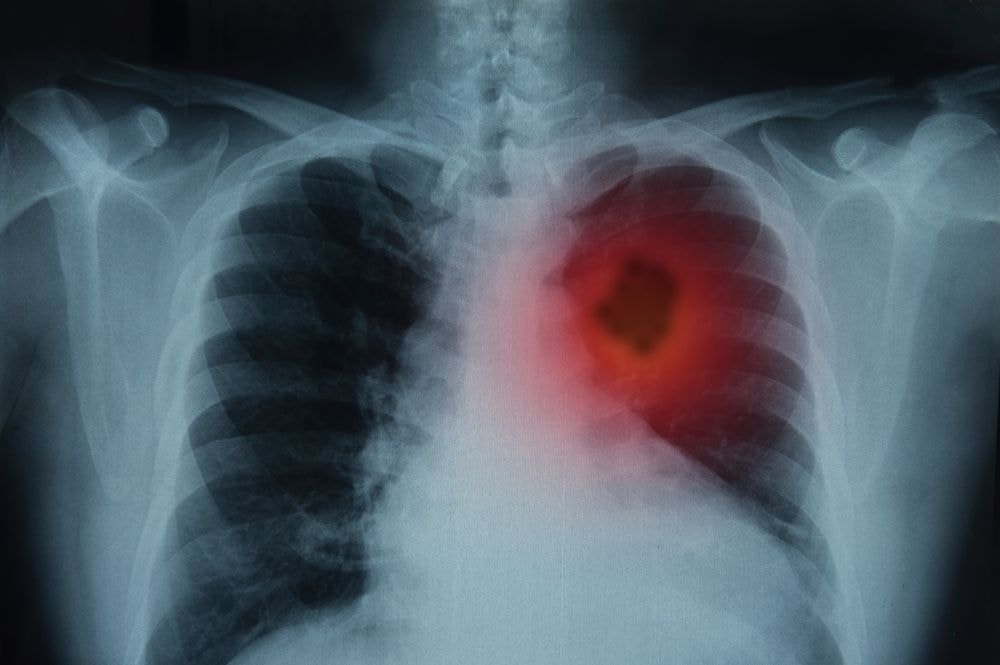

Mimo zaawansowanych terapii i metod profilaktycznych medycyna wciąż nie potrafi wygrać z rakiem. Co roku na świecie z powodu chorób nowotworowych umiera 8 mln osób. W Polsce rak zabija ponad 100 tys. osób rocznie. Ta ponura statystyka zacznie się zmieniać na lepsze dzięki immunoterapii. To innowacyjna metoda leczenia polegająca na wzmocnieniu naturalnych reakcji obronnych organizmu. – Immunoterapia jest rzeczywistym przełomem. Jej mechanizm jest uniwersalny w leczeniu kilku typów nowotworów, a poza tym jest to metoda, która może zapewniać długotrwałą kontrolę lub wyleczenie zaawansowanych przypadków nowotworów – mówi prof. dr hab. Piotr Rutkowski, Kierownik Kliniki Nowotworów Tkanek Miękkich, Kości i Czerniaków, Centrum Onkologii-Instytutu im. Marii Skłodowskiej-Curie w Warszawie.

W tym celu badacze używają tzw. przeciwciał monoklonalnych, które blokują działanie wspomnianych cząsteczek na powierzchni komórek rakowych. Skuteczność immunoterapii została udowodniona podczas badan klinicznych III fazy u chorych na czerniaka, niedrobnokomórkowego raka płuca i raka jasnokomórkowego nerki. Badania nad leczeniem innych nowotworów trwają. Coraz częściej lekarze próbują również immunoterapii skojarzonej, czyli